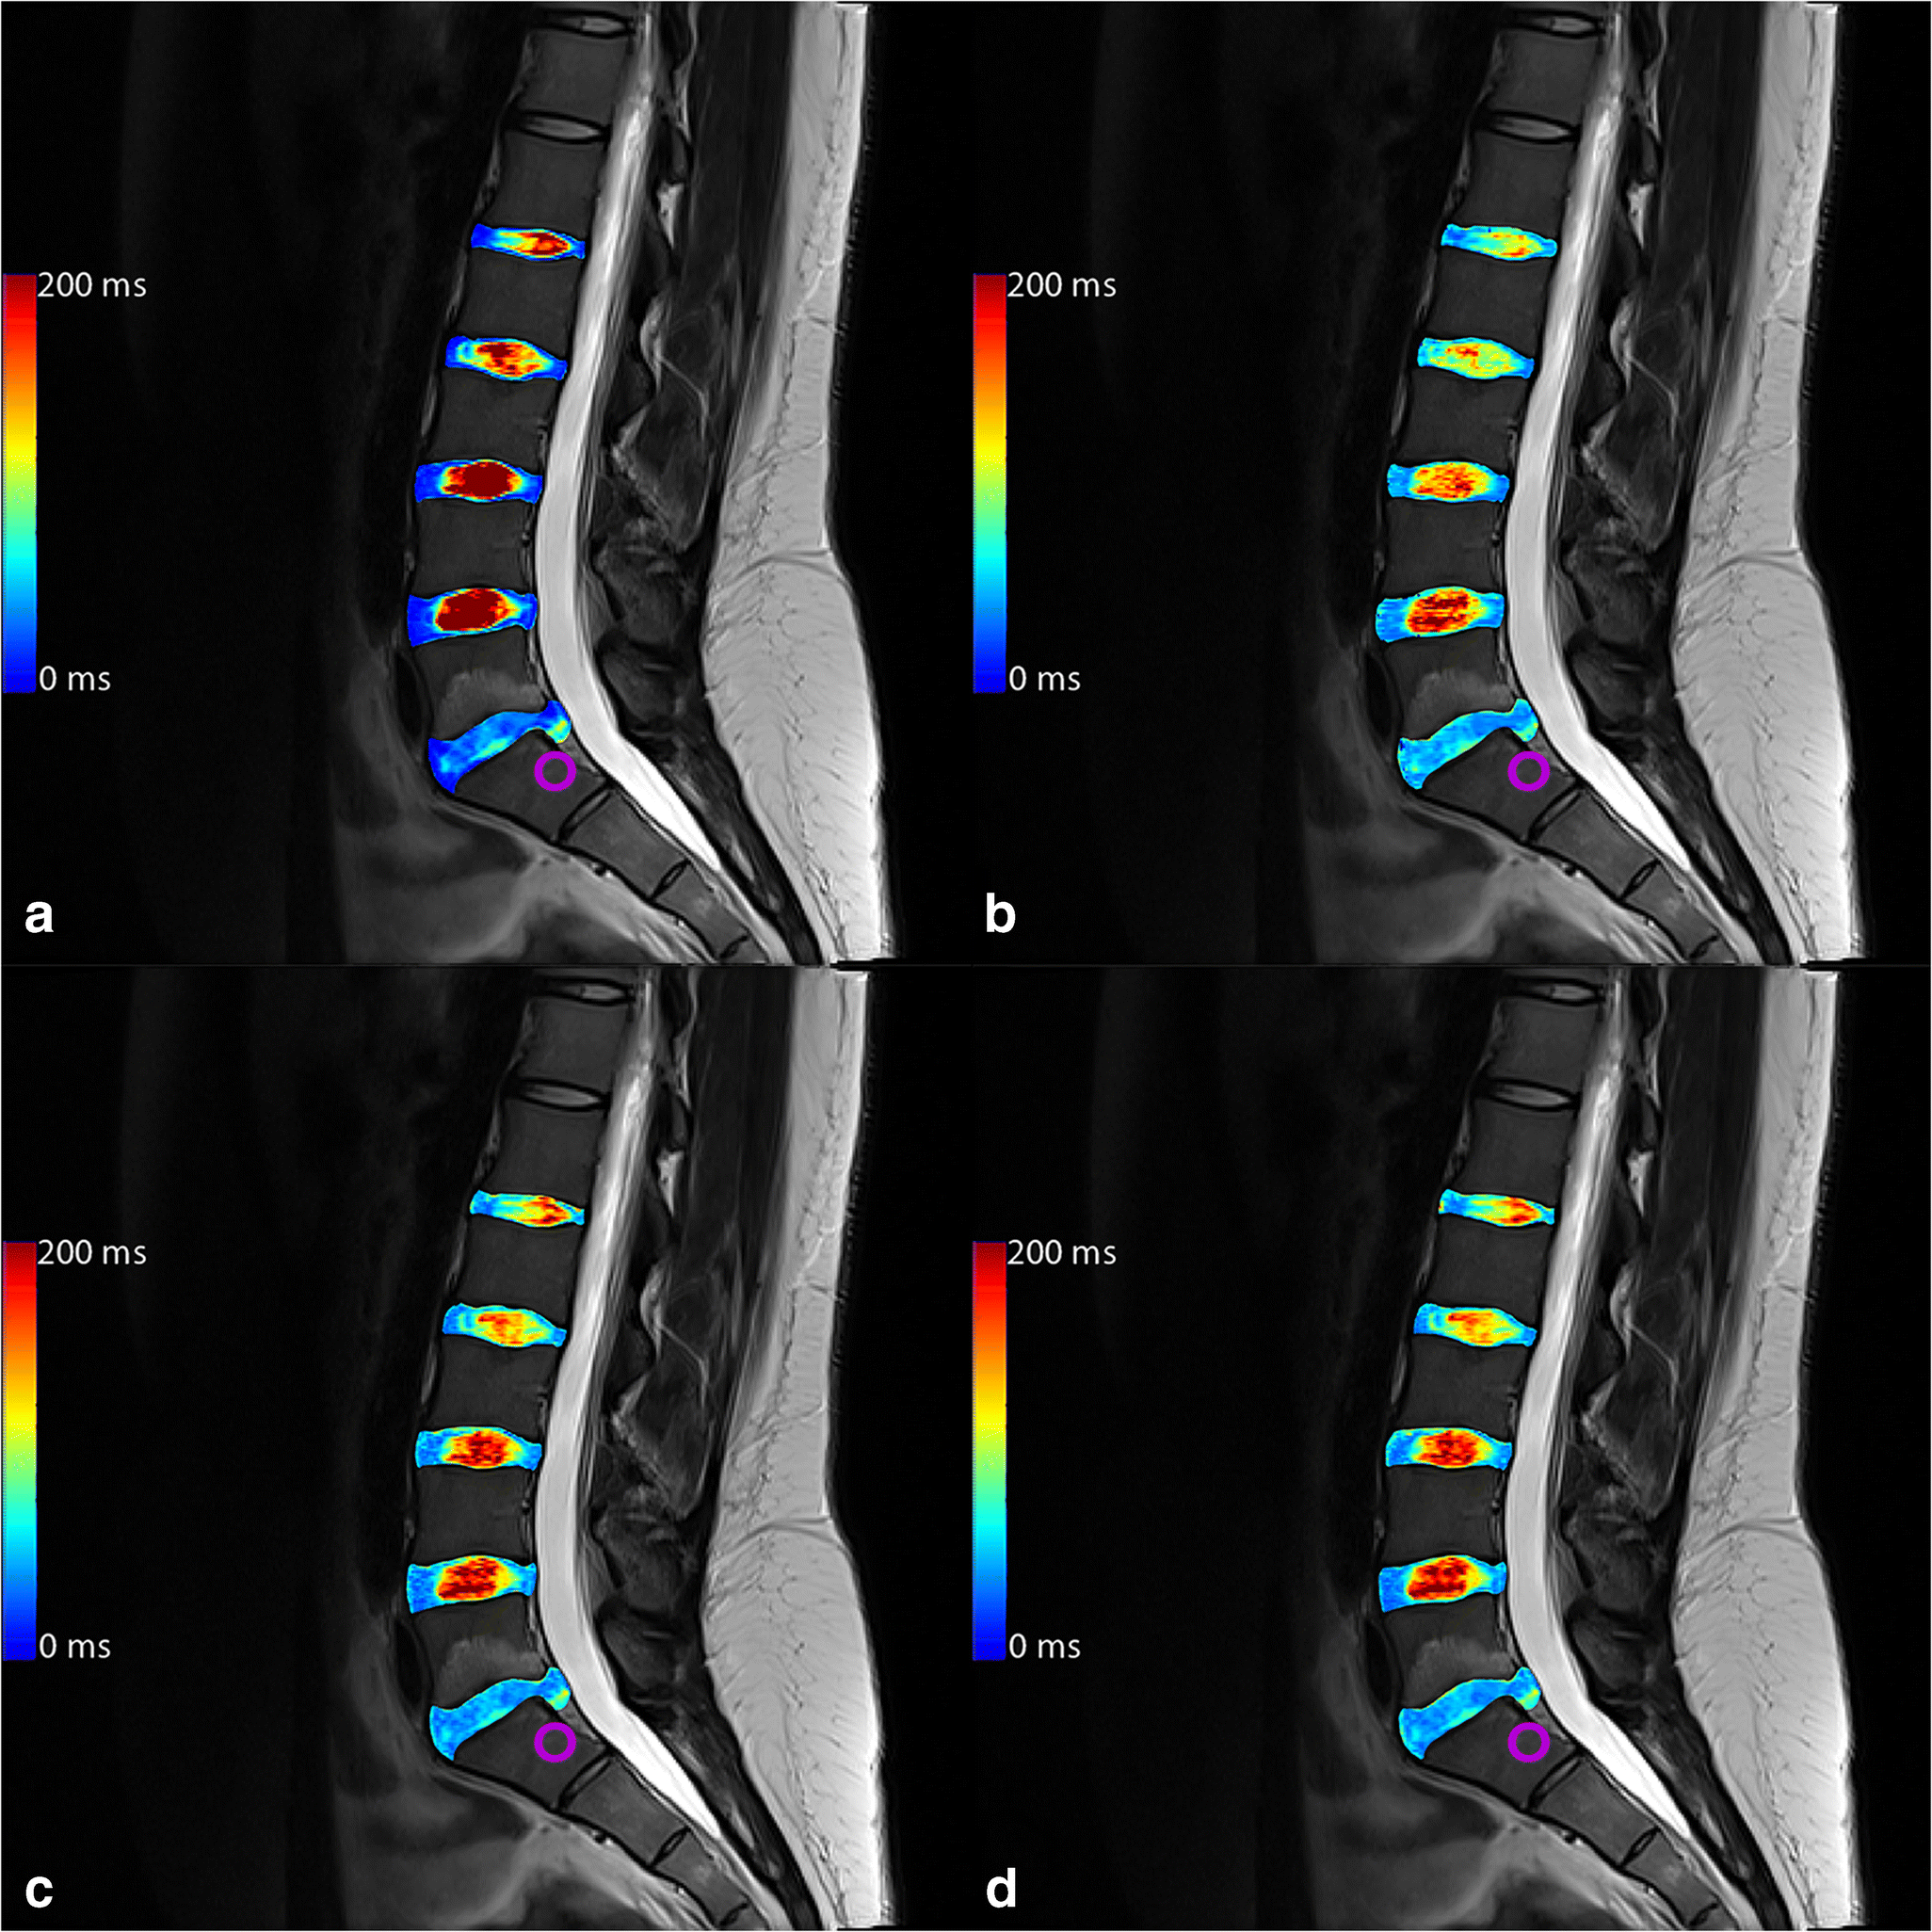

Calculating an ROC for HIZ for the nucleus pulposus T2, the AUC was 0.919 (0.886–0.953) for T2-GRAPPATINI, 0.913 (0.873–0.953) for T2-MESE, 0.911 (0.871–0.950) for T2-EVEN, and 0.915 (0.876–0.954) for T2-WO1ST. An example patient with a combination of lumbar disc herniation and annular tear of the L5/S1 segment alongside a HIZ in the L4/L5 segment is given in Fig. 3 with color-coded T2 map overlays.

Fig. 3

Color-coded T2 map overlays of a multi-echo spin-echo (MESE), b GRAPPATINI, c EVEN, and d WO1ST. The red asterisk marks a high-intensity zone in L4/L5 which can be clearly seen in all measurements (another small one tear can be seen on L3/L4 also). The purple circle marks a herniating L5/S1 disc with annular tear with nucleus pulposus tissue in the lower posterior annular region of interest, resulting in higher, pathological T2 at that very place